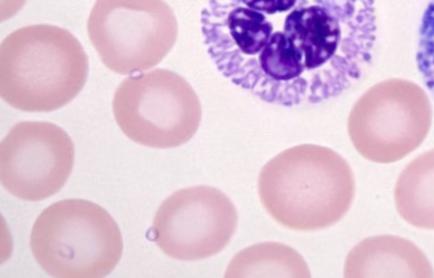

Malaria

Rapid parasite detection and quantification in thick and thin blood films with species identification capability